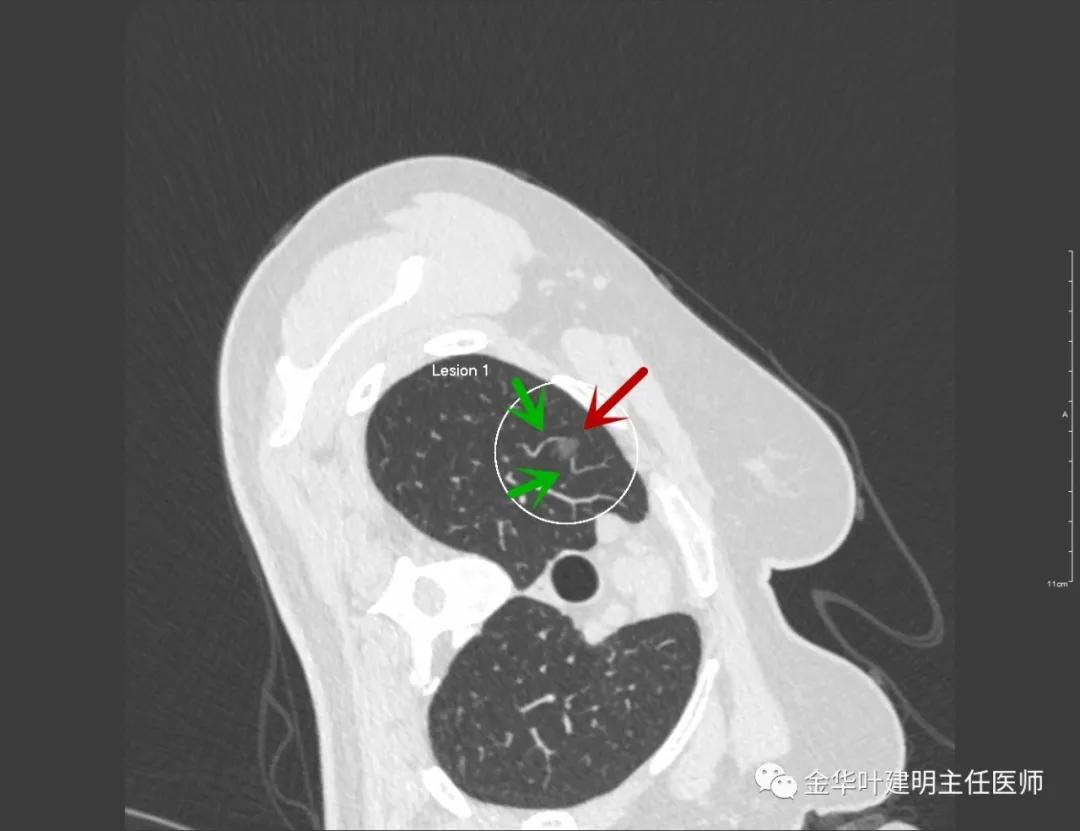

靶扫描示明显血管进入病灶

因为横断面的关系,红色箭头示尖段支气管的开口,绿色箭头示后段支气管